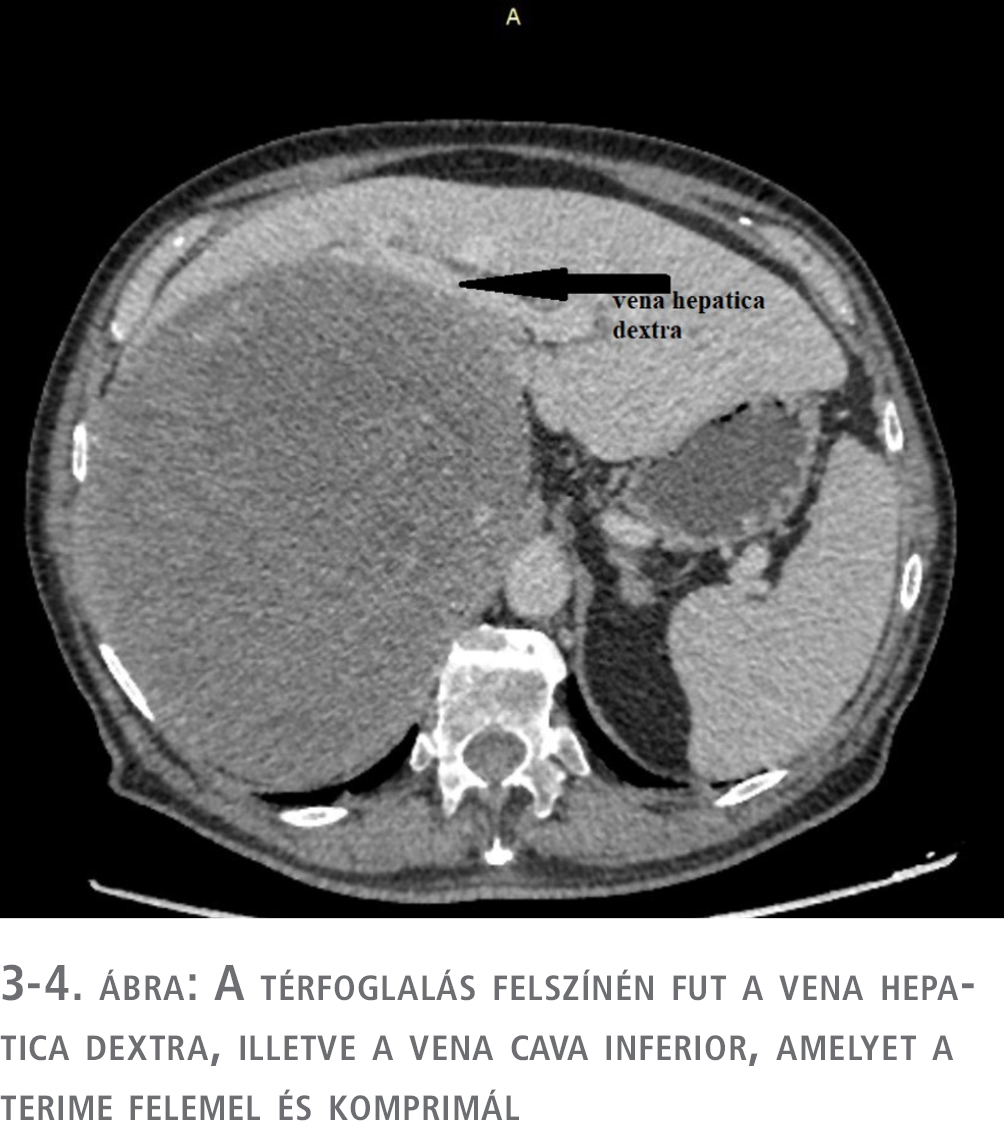

A CT eredménye alapján a szakrendelőből a beteget sürgősséggel az endokrinológiai osztályra utalták további kivizsgálás céljából. Az endokrinológiai osztályos kivizsgálás során ismét CT-vizsgálatot végeztek, amely a térfoglalás májeredetét elvetette, és halmozási dinamikája alapján elsősorban adrenocorticalis carcinomának véleményezte (1–4. ábra). A hormonprofil alapján hormontermelésre utaló eltérés nem igazolódott. ACTH-, DHEA-S-, kortizol-, CgA- és vizeletmetanefrin-szintek meghatározása, valamint negatív eredményű dexametazonszuppressziós teszt történt. A vizsgálatok és a klinikai kép alapján hormontermelő tumor nem igazolódott. Biopsziát nem végeztek, tekintve, hogy terápiás konzekvenciája nem lett volna sem malignus, sem malignitás nélküli eredmény esetén: a terime mérete alapján malignitási potenciálja nagy, ily módon műtéti ellátása csak malignusnak tekintve történhet.

A máj balra diszlokálódott, a jobb cranialis szegmentumai elsorvadtak, a térfoglalás a vena cava inferiort felemelte és komprimálta, a vesét caudalis irányba diszlokálta. A máj mobilizálása után a terime fluktuáló részletéből intraoperatív citológiai mintát küldtünk, amely a vérből alakos elemeket és kevés histiocytát tartalmazott, így malignitást sem kizárni, sem megerősíteni nem tudtunk, így a térfoglalást továbbra is potenciálisan malignusnak tekintve, onkológiai-sebészeti elvek alapján in toto eltávolítás mellett döntöttünk (6. ábra).

Enormis méretű vagy jelentős hormonaktivitású mellékvese-térfoglalások esetén multidiszciplináris team szükséges a kivizsgálás és a perioperatív ellátás során. A műtéti ellátás során a teamnek mind aneszteziológiai, mind sebészi oldalról felkészültnek kell lennie a váratlan intraoperatív kihívásokra és komplikációkra, amelyek a nem hormontermelő, de nagyméretű tumorok esetén leggyakrabban a vena hepatica, a vena cava inferior, illetve a vena renalis sérüléséből fakadó masszív vérzés, illetve a dekompresszióból adódó keringés-összeomlás lehetnek.